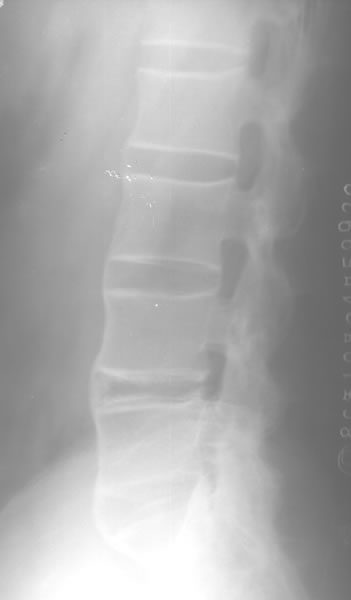

强直性脊柱炎(方形椎)

图片尺寸884x917